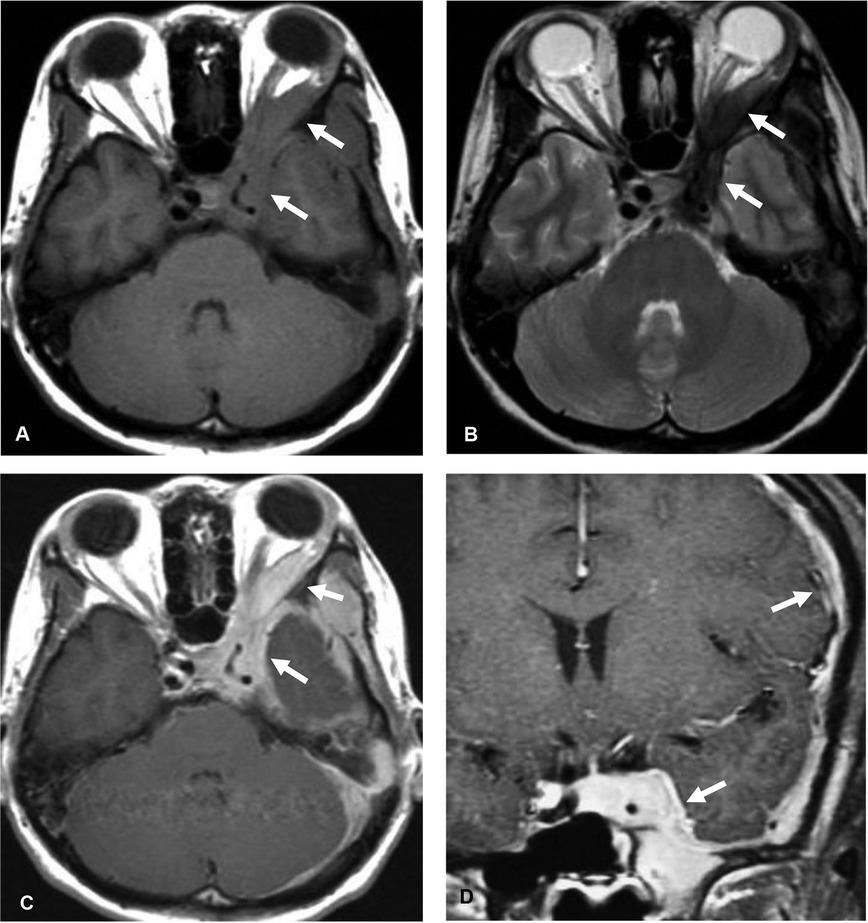

Figure 1